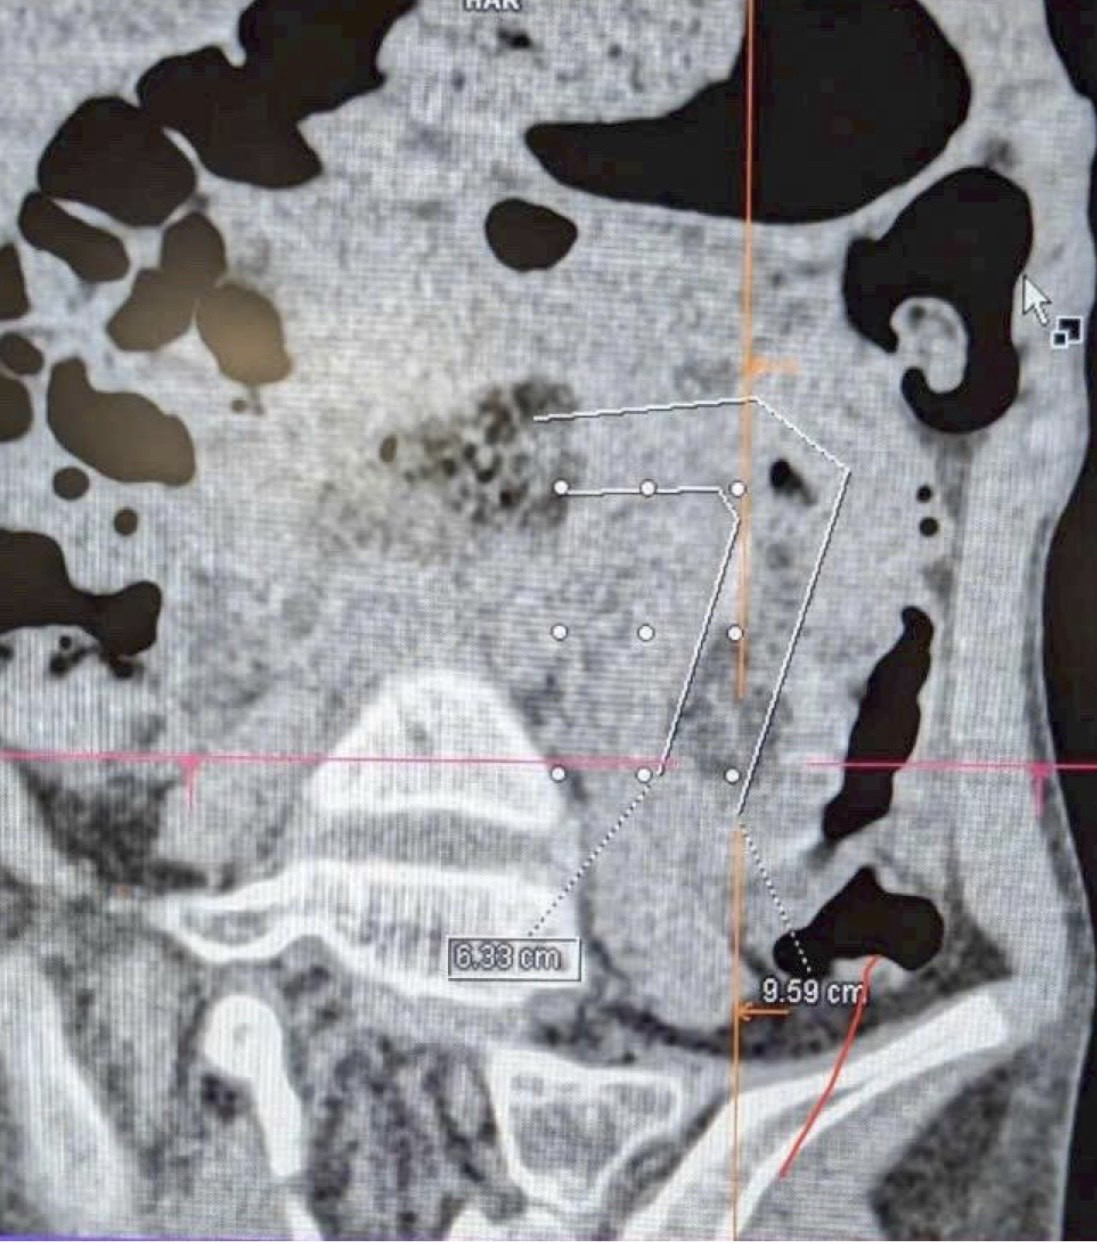

Hình ảnh CT Scan phát hiện ra búi tóc và tình trạng tắc ruột của bệnh nhân. Ảnh:FV

Bé H. (9 tuổi, TP.HCM) được gia đình đưa đến Bệnh viện FV trong tình trạng đau bụng nhiều ngày, nôn ói liên tục, người gầy và da xanh xao. Những biểu hiện ban đầu dễ khiến mọi người nghĩ đến rối loạn tiêu hóa, nhưng kết quả khám chuyên sâu và hội chẩn giữa các bác sĩ Ngoại tổng quát - Tiêu hóa - Chẩn đoán hình ảnh cho thấy nguyên nhân nghiêm trọng hơn nhiều: trong bụng bé có một búi tóc dài gần 1m, bện chặt như dây thừng, kéo từ dạ dày xuống ruột non và gây tắc hoàn toàn.

Các bác sĩ lý giải, tóc không thể tiêu hóa được, nên sau nhiều năm, lượng tóc nuốt vào tích tụ lại thành một khối đặc cứng, bện chặt như dây thừng, bít tắc đoạn ra của dạ dày và gây tắc ruột hoàn toàn.